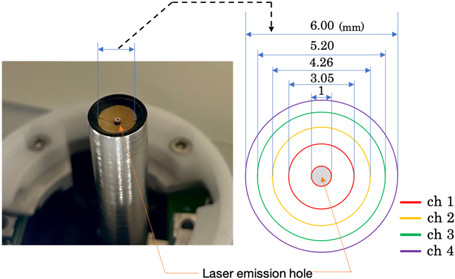

Standard image High-resolution imageThe annular array transducer had a concave surface with a geometric focus of 6 mm and a center hole (ϕ1 mm) for the laser outlet. The concave geometry was divided into four ring-shaped PZT elements (a center frequency of 60 MHz  20%) with a minimum diameter of 1 mm and a maximum diameter of 6 mm as shown in Fig. 2. The Nd:YAG laser was selected to irradiate 532 nm pulsed beams at a repetition rate of 1 kHz and a pulse width of 1.2 ns. The emitted pulse energy was measured to be 16 μJ pulse−1. While the PA transmitter/receiver unit was raster-scanned by the XY stage, an event of emitting a laser pulse and receiving PA signals was repeatedly performed to acquire the three-dimensional distribution of the optical absorbers in the imaging field. In each receiving event, the PA waves generated at the object by the laser irradiation were received by each element of the annular array transducer and recorded at a sampling frequency of 500 MHz.

20%) with a minimum diameter of 1 mm and a maximum diameter of 6 mm as shown in Fig. 2. The Nd:YAG laser was selected to irradiate 532 nm pulsed beams at a repetition rate of 1 kHz and a pulse width of 1.2 ns. The emitted pulse energy was measured to be 16 μJ pulse−1. While the PA transmitter/receiver unit was raster-scanned by the XY stage, an event of emitting a laser pulse and receiving PA signals was repeatedly performed to acquire the three-dimensional distribution of the optical absorbers in the imaging field. In each receiving event, the PA waves generated at the object by the laser irradiation were received by each element of the annular array transducer and recorded at a sampling frequency of 500 MHz.

Fig. 2. (Color online) The annular array transducer.